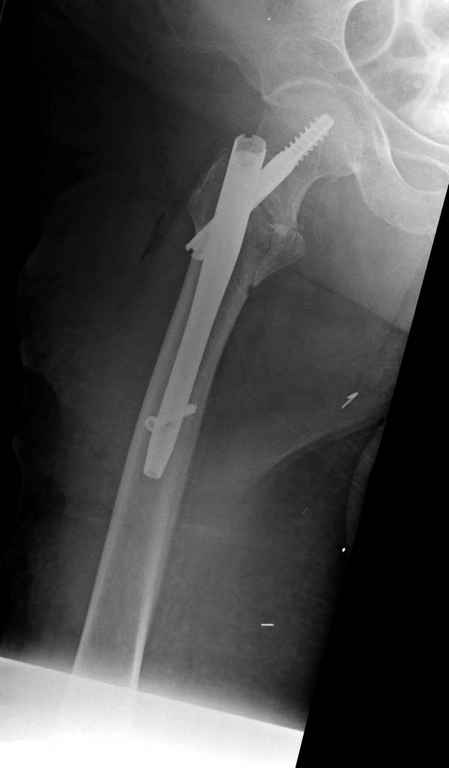

Перелом тут больше подвертельный. Нагрузка без торцевого упора на уровне перелома привела к телескопированию отломков на стержне. Ну и варус небольшой тоже свою лепту внес - если бы его не было, контактирующие латеральные стенки обоих отломков предотвратили бы укорочение, да и срослось бы за пару месяцев. А раз не срослось, упора отломков нет, более слабым местом оказались не нижние винты, а кость в головке и шейке. Так что надо было хотя бы удалить нижние винты до начала полной нагрузки.

Фиксация * reversed obliquity* подвертельных переломов - дело непростое.

На мой взгляд, причиной телескопирования явилось несоответствие диаметра гамма нэйл с диаметром канала подвертельного отдела бедра: обратите внимание на величину протрузии шеечного винта и величину медиализации дистального фрагмента - они одинаковы, смещение или телескопирование фрагментов происходило до того момента, пока гамма нэйл не упёрся в медиальный кортекс и образовалось пространство между латеральным

кортексом и латеральной поверхностью гвоздя.

E> На мой взгляд, причиной телескопирования явилось несоответствие

E> диаметра гамма нэйл с диаметром канала подвертельного отдела бедра:

Диаметр гаммы в диафизарной части ~11 мм. А диаметр канала, тем более у пожилых с остеопорозом, может быть мм 15. Даже рассверливать обычно не приходится, после формирования широкого канала в вертельной области можно сразу толкать гвоздь, он влетает, как карандаш в стакан. Так что соответствия диаметров не бывает никогда. Однако представленная ситуация случается далеко не каждый раз. Если гвоздь в центральном отломке входит чуть медиальнее верхушки вертела, и идет вдоль передне-латеральной стенки центрального отломка, то все будет хорошо.

Здраствуйте. По данному снимку видно 2-а основных момента которые привели к протрузии винта в вертлужную впадину: 1) шеечный винт дистальной поверхностью наружнего края "зацепился" за латеральный кортикал бедра, это не дало сработать динамической системе гвоздь-винт. 2) лучьше шеечный винт проводить ближе к дуге Адамса, там болееплотная костная ткань. Решенее: как подготовка к эндопротезированию, реостеосинтез, можно такой же системой, но с учетом упомянутых моментов, максимальное безнагрузочное ЛФК (без боли).